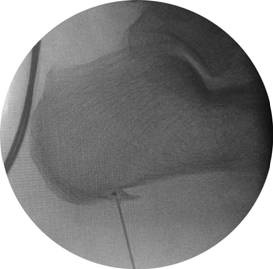

手术前,可以清晰可见足跟底部骨刺(针头所致之处)

手术中,关节镜下寻找骨刺(骨赘)

手术中,关节镜下磨去骨赘

手术后,可以清晰可见足跟底部骨刺完全去除(针头所致之处)